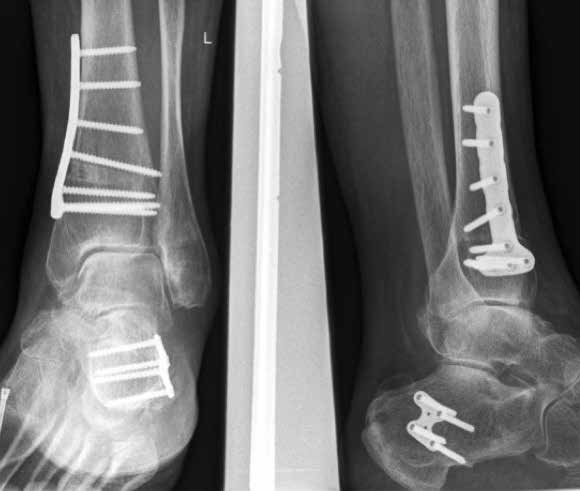

Weiterhin führen Fehlstellungen im Rückfuß zu statischen und dynamischen Überlastungen, da sich bei Varusfehlstellung (Abb. 2a) das Zentrum der Kraftübertragung nach medial und bei Valgusfehlstellungen nach lateral verlagert 47. Die Achillessehne wirkt durch ihren Zug zusätzlich invertierend bei Varusfehlstellung und evertierend bei Valgusfehlstellung auf den Rückfuß ein 48. Möglichkeiten der operativen Therapie sind entweder die einfache Umstellungsosteotomie der distalen Tibia und Fibula als rein supramalleoläre Osteotomie mit dem Ziel einer Überkorrektur des distalen Tibiagelenkflächenwinkels von 3 bis 5° 49 oder die kombinierte Osteotomie an Bein und Rückfuß (Abb. 2b) mit oder ohne Weichteileingriff je nach Topographie der Achsfehlstellung 50. Weitere Möglichkeiten sind die Calcaneusosteotomie, meist als ergänzende Osteotomie nach Wiederherstellung der korrekten Achse (Abb. 2b) im Sinne einer Verschiebeosteotomie, um die Zugrichtung der Achillessehne zu zentrieren, und die Osteotomie der medialen Säule, die bei durch Valgusfehlstellung induzierter Abflachung des medialen Längsgewölbes indiziert sind. Hierbei werden zusätzlich korrigierende Arthrodesen des I. Strahls (Naviculo-cuneiforme-Gelenk, Tarsometatarsalgelenk) oder plantarflektierende Osteotomien (Cuneiforme I oder Metatarsale I) durchgeführt 51.

Arthrodese

In ausgeprägten Fällen von Arthrose, oft mit Instabilität im oberen Sprunggelenk (Abb. 7), schwerwiegendem Funktionsverlust und starker Schmerzausprägung, ist nach wie vor die Arthrodese die Therapieoption der Wahl. Dadurch sollen die Achskongruenz wiederhergestellt und die Schmerzen eliminiert werden. Gleichzeitig bedeutet dieser Schritt jedoch, dass keine weitere operative Eskalation mehr möglich ist. Meist kommen die tibiotarsale oder tibiatalar-calcaneare Arthrodese zum Einsatz. Entscheidend für die Wahl des Arthrodeseverfahrens sind der Schweregrad der degenerativen Gelenkveränderungen, der Schmerz und die Stellungsverhältnisse im Subtalargelenk.

Eine Sonderform stellt die Talusnekrose dar, die ebenfalls zu schwerwiegenden Destruktionen und Achsfehlstellungen im OSG führt. Das Mittel der Wahl im fortgeschrittenen Stadium (Abb. 8a) ist hier die Arthrodese des OSG und des unteren Sprunggelenks (USG) mittels Arthrodesennagel (Abb. 8b).

Während der Eingriff meist in einer guten Funktion und einer Schmerzeliminierung resultiert, muss jedoch im Laufe der Zeit mit Anschlussarthrosen gerechnet werden. Aufgrund dessen sollten alle Patienten nach Arthrodese des oberen Sprunggelenkes mit Einlagen und Abrollhilfen am Konfektionsschuh (Abb. 4) versorgt werden. Ziel ist es, dadurch ein harmonisches Gangbild zu erreichen und die einwirkenden Kräfte auf die Anschlussgelenke zu minimieren.